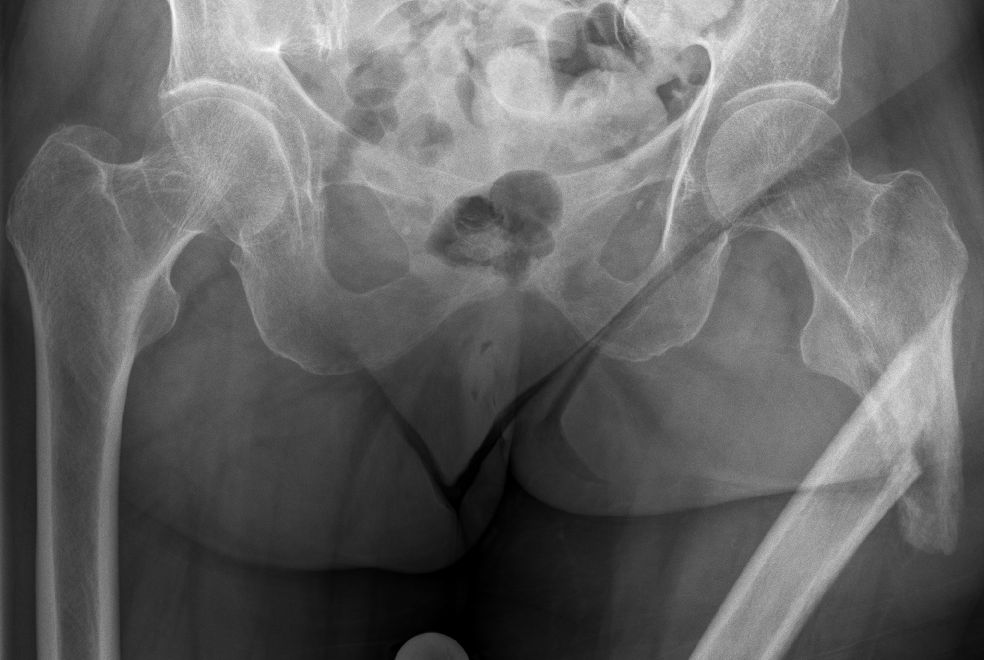

Pathologische subtrochantäre Fraktur bei extranodalem, intraossärem DLBCL.